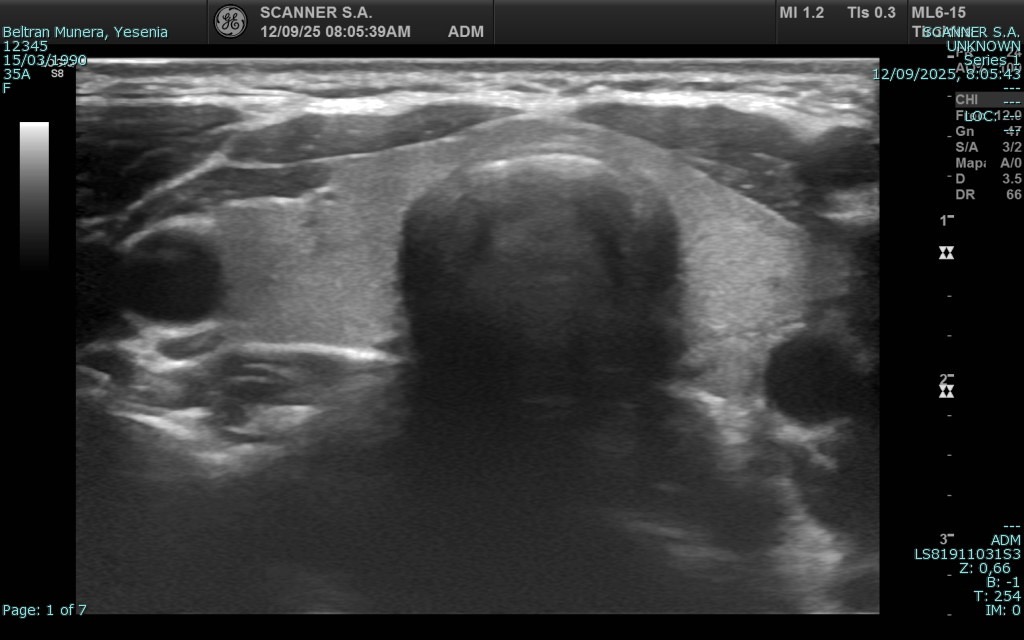

La ecografía es una técnica de diagnóstico por imagen no invasiva que utiliza ondas de ultrasonido para visualizar en tiempo real órganos, tejidos blandos y estructuras internas del cuerpo. A diferencia de otros estudios, no emplea radiación, lo que la convierte en una herramienta segura, ampliamente utilizada en diversas áreas médicas para detectar alteraciones, monitorear enfermedades y apoyar decisiones clínicas con agilidad y precisión.

En SCANNER S.A. contamos con equipos ecográficos de alta resolución, diseñados para ofrecer imágenes claras y detalladas. Nuestro servicio incluye tanto ecografía general como ecografía especializada, permitiendo realizar estudios abdominales, pélvicos, ginecológicos, obstétricos, renales, tiroideos, de partes blandas, musculoesqueléticos y más.